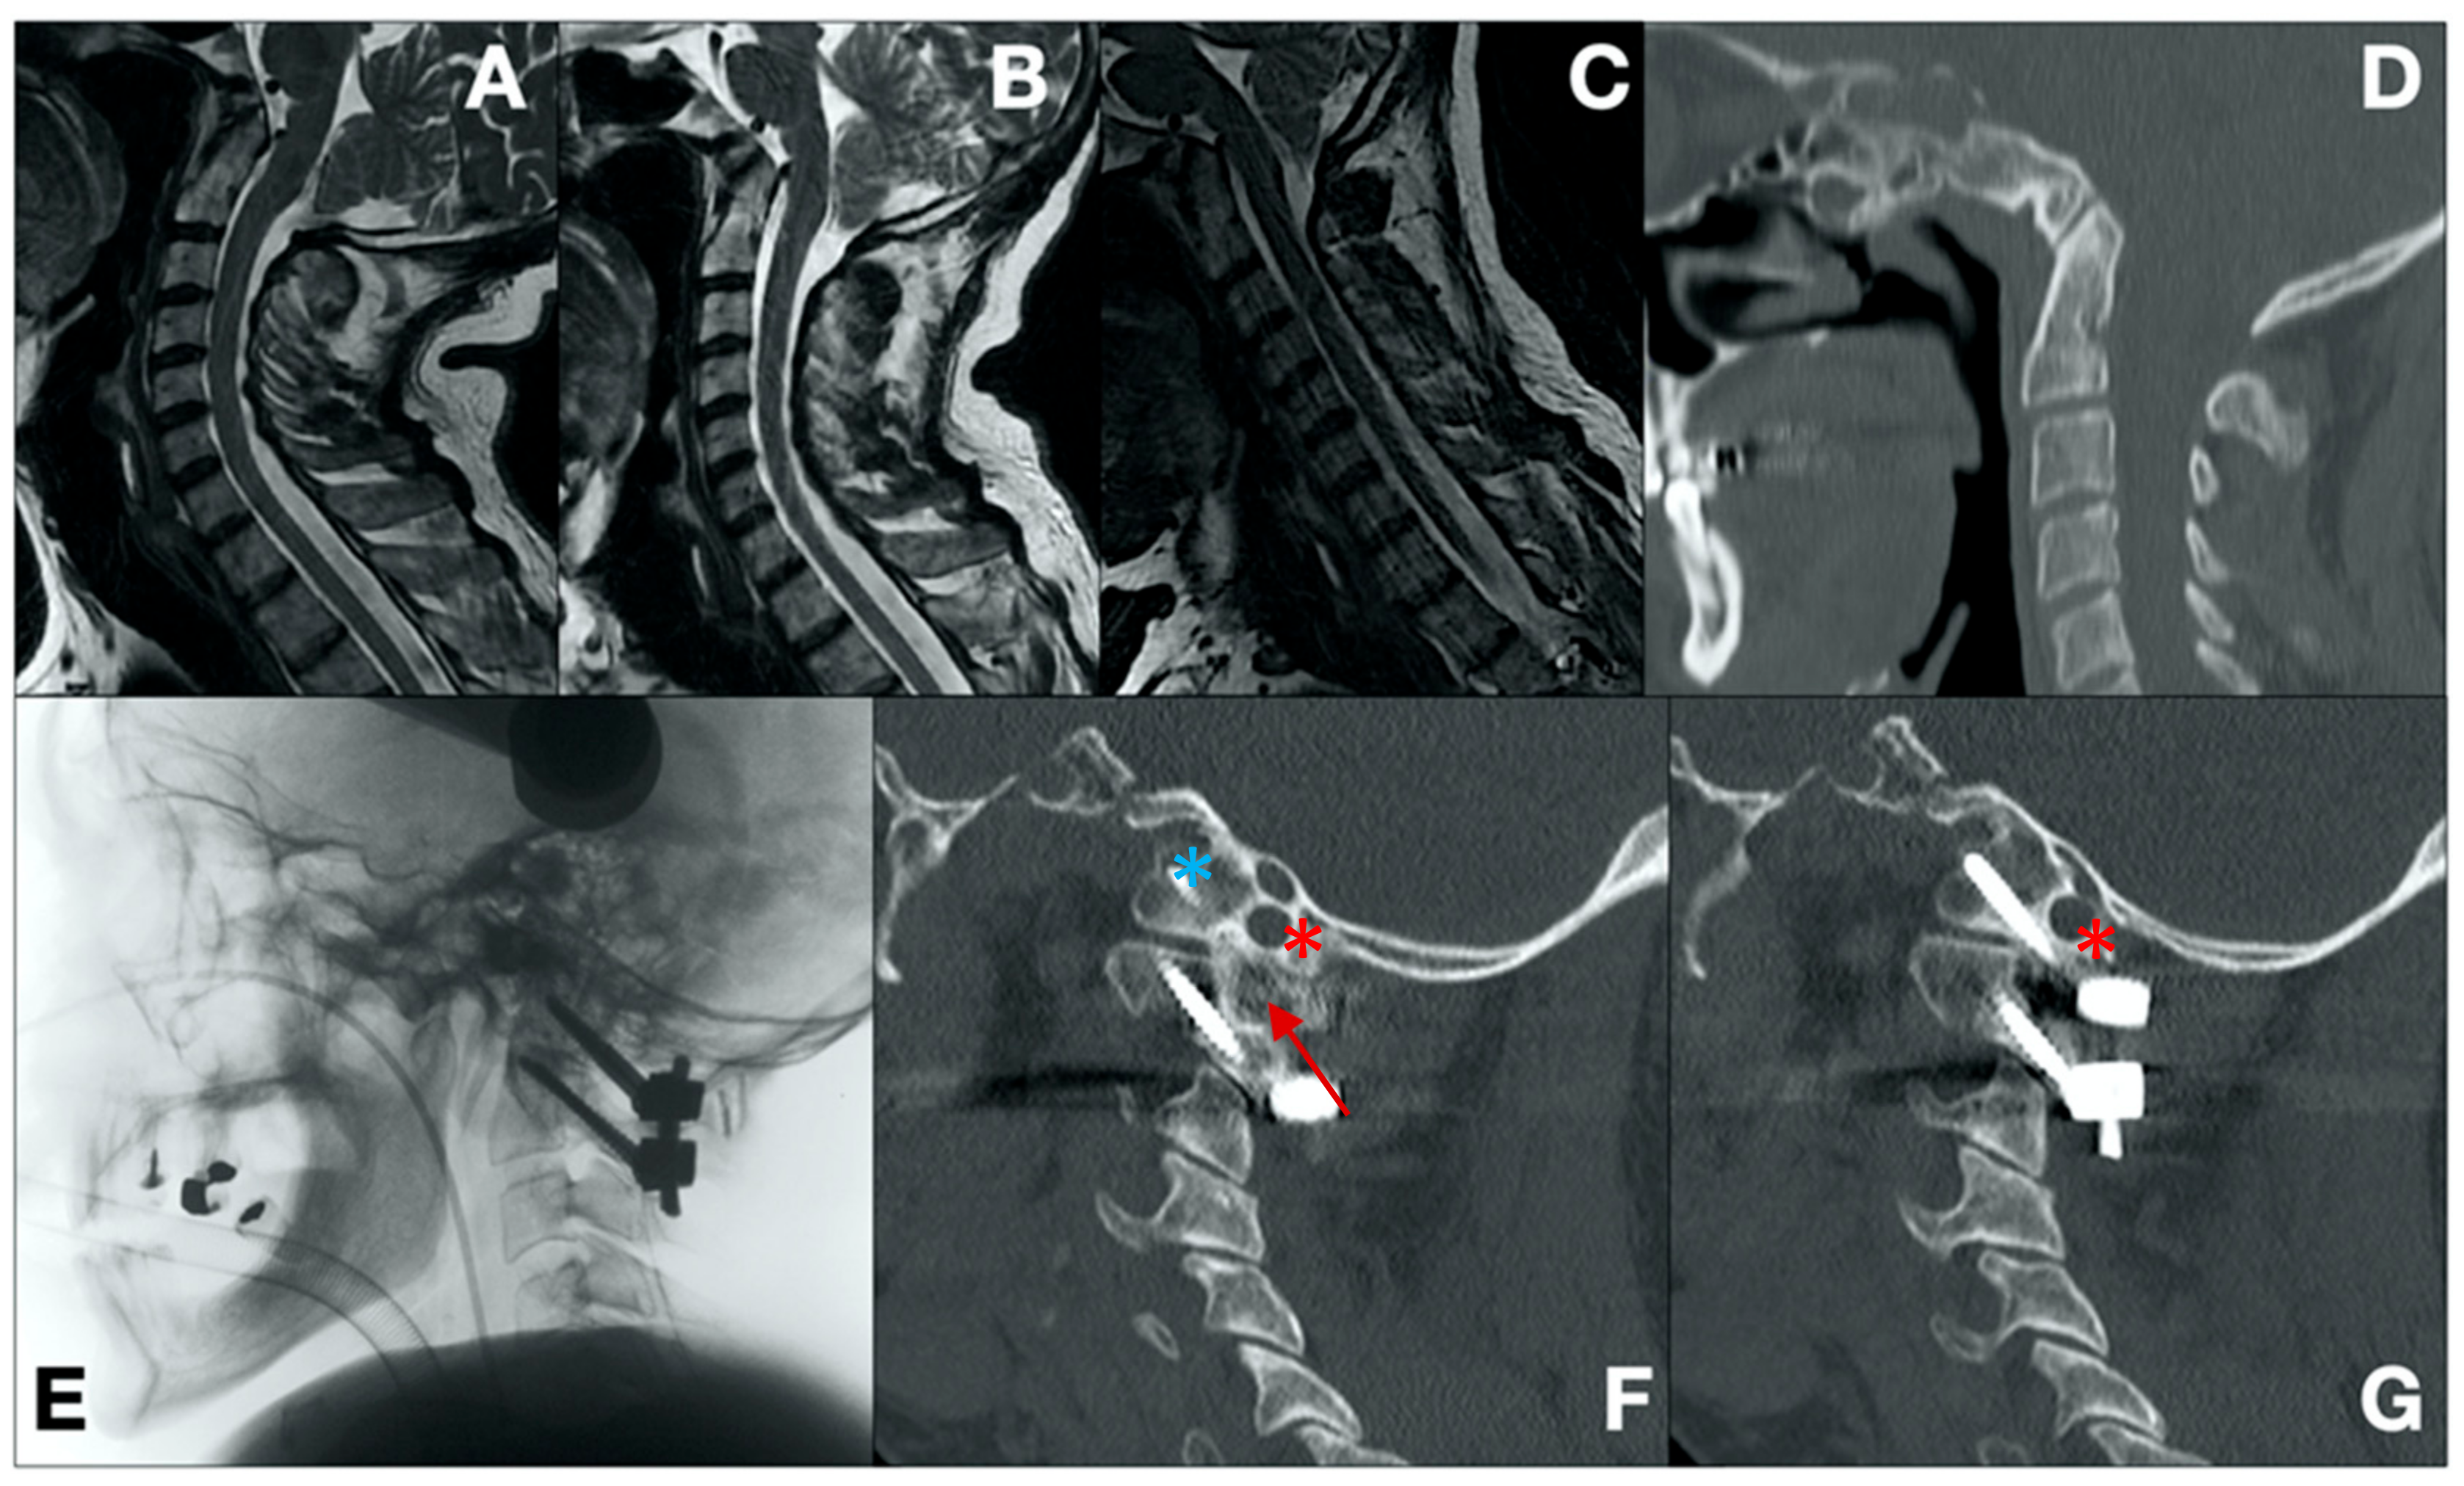

- Case 1 (Figure 1)